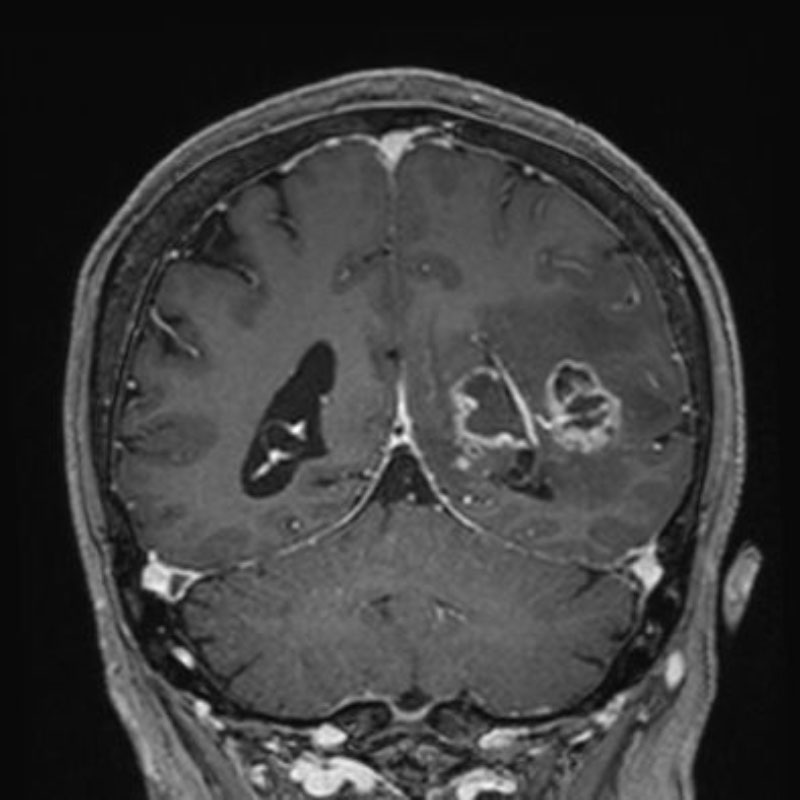

678

'25年10月

70代

脳腫瘍

頭蓋内腫瘍摘出術

No.’25_80 手術前1

No.’25_80 手術前2